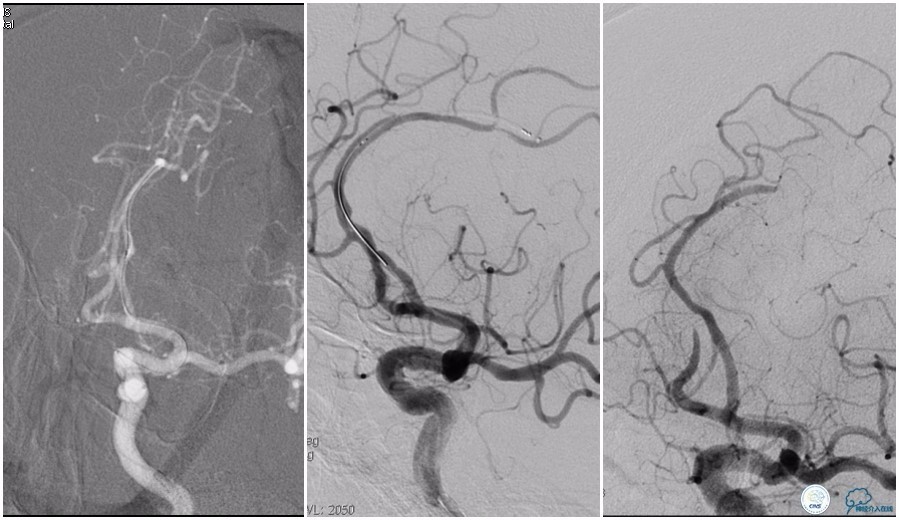

12:35穿刺成功,TOT 185min。3型主动脉弓,右侧颈内动脉起始部狭窄70%,右侧大脑前动脉A1段未显影。

双侧大脑前动脉A4段闭塞,右侧大脑前动脉由左侧大脑前动脉经前交通动脉代偿供血。

6F Envoy置于颈内动脉C3段,选用Solitaire-FR 4*20mm支架释放于右侧大脑前动脉,完全覆盖血栓。